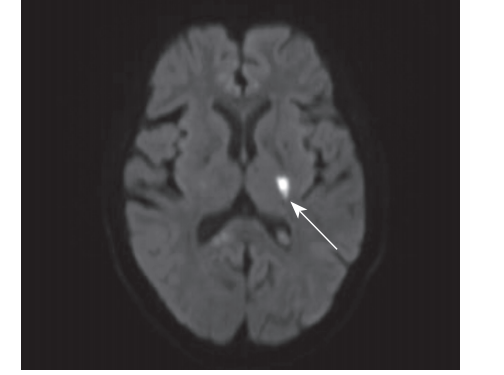

入院后化验检查:血常规示血小板计数:89×109/L。尿蛋白:0.16 g/24 h。肾小管3项:β2-MG 2051.30μg/L,尿 NAG 14.00 U/L。尿酸化含量测定:pH值 6.20,可滴定酸 5.33 mmol/L,铵离子 28.25 mmol/L。血沉 23 mm/h。Coombs 2+。抗心磷脂抗体:10.2 U/mL(0~10 U/mL);抗β2糖蛋白 1 抗体:52.55 RU/mL (0~20 RU/mL);狼疮抗凝血因子检测标准化 dRVVT比值:1.07;抗磷脂酰丝氨酸/凝血酶原 aPS/PT IgM、IgG 均阳性;抗核小体抗体检测:374.24 RU/mL (0~20 RU/mL),抗 dsDNA 抗体 186.4 IU/mL。抗核抗体:1:320 均质;抗 SSA (+);抗Ku抗体 (+++);冷球蛋白阳性;免疫球蛋白 IgA:5.74 g/L,免疫球蛋白IgG:17.68 g/L,补体C3:0.53 g/L,补体C4:0.06 g/L,补体C1q:138 mg/L。血气分析、肝、肾功能、电解质正常,凝血功能、糖化血红蛋白、同型半胱氨酸、蛋白C 、蛋白S未见异常。头颅 MRI及MRA示(见图1)“左侧基底节区梗死灶(急性-亚急性期);颅内动脉轻度硬化表现”。颈动脉超声示“双侧颈动脉硬化并右侧斑块形成”。唾液腺彩超示“腮腺及颌下腺弥漫性病变”。甲状腺彩超示“甲状腺双叶多发囊实性结节”。四肢静脉彩超未见异常。胸腹盆增强 CT 示“双肺间质纤维化;双肺多发结节;双侧锁骨下、腋窝、纵隔内多发淋巴结;肝 S6段血管瘤;双肾多发结石”。心电图示“QT 间期延长”。心脏彩超示“节段性室壁运动异常”。冠状动脉CTA未见明显异常。心脏MR增强示“左心室运动稍减弱,二尖瓣、主动脉瓣区轻度返流”。肺功能示“肺部通气及弥散功能障碍 (DLCO-SB 40.6%)”。(左前臂)皮表切除标本示“送检小块皮肤组织,真皮内多量胶原纤维沉积”。

图1 头颅磁共振弥散加权成像示左侧基底节区梗死灶(急性-亚急性期),白色箭头示梗死灶

诊疗经过:病人此次因突发右侧肢体无力入院,结合症状、体征及影像学改变(头颅 MRI 示左侧基底节区DWI高信号),考虑急性脑梗死诊断明确。给予阿司匹林抗血小板、阿托伐他汀降脂及活血药物等对症治疗。